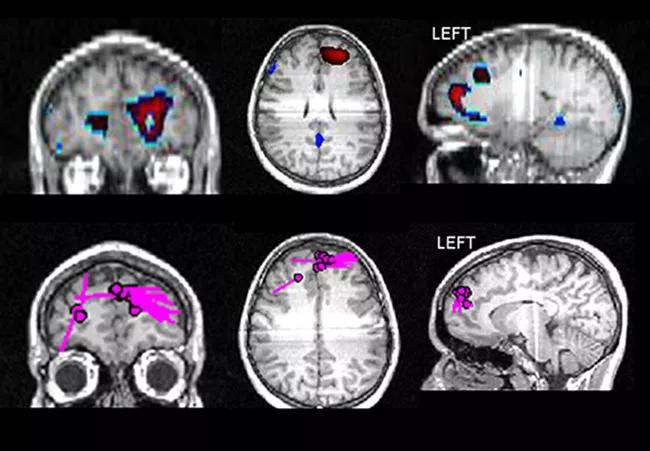

Drawing further attention to this area are the findings on ictal SPECT, with left anteromesial frontal hyperperfusion during a seizure, and findings on magnetoelectroencephalogram (MEG), which show a cluster of rare dipoles in the same region (Figure 2).

16-neu-1856-inset2

Figure 2. Left frontal localization supported by noninvasive testing with FDG-PET (top), ictal SPECT (middle) and magnetoencephalography (bottom)